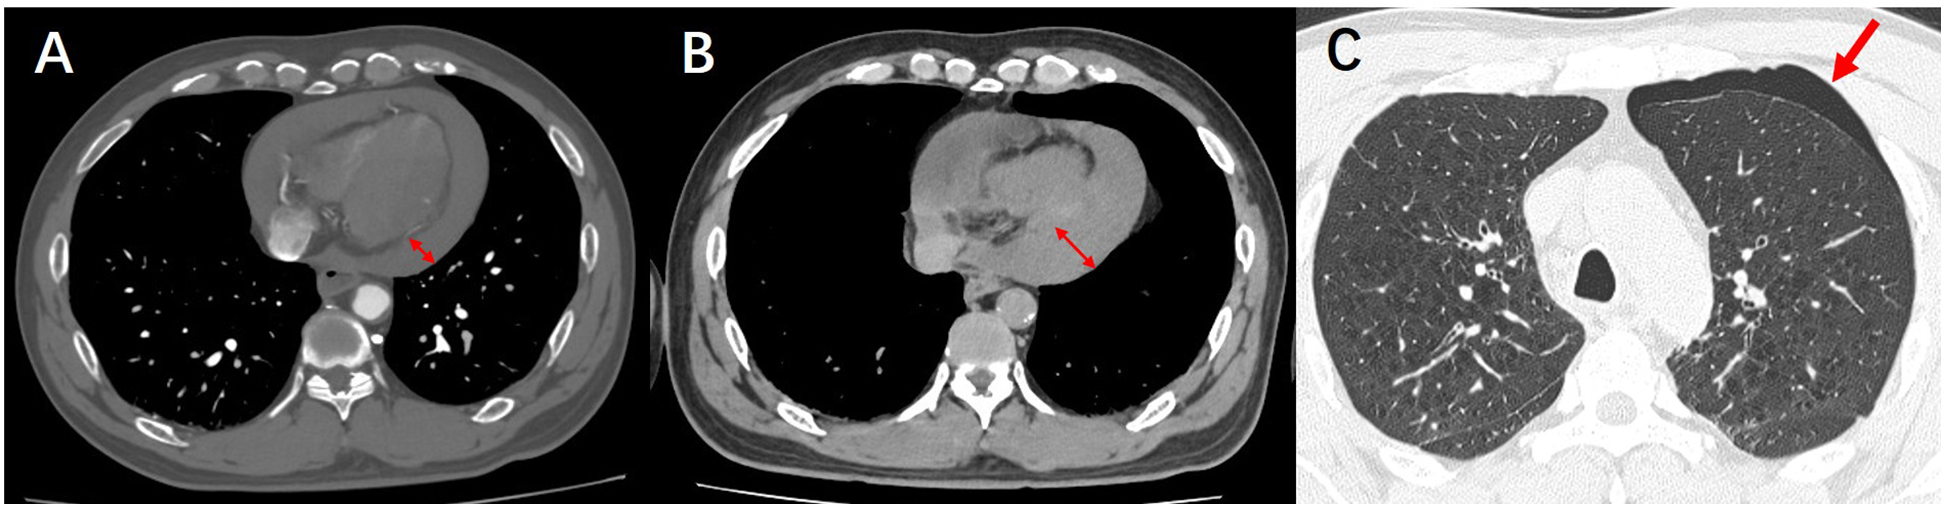

The patient's symptoms of generalized cyanosis and dyspnea have been increasing. The patient was then transferred to the cardiac care unit (CCU) for ultrasound-guided pericardiocentesis. After transfer to the intensive care unit, the patient's ultrasound-guided pericardiocentesis remained unsuccessful due to a large amount of gas interference in the chest cavity. Given the possibility of pneumothorax, the patient underwent a computed tomography (CT) scan of the lungs (Figure 4). Pulmonary CT indicated pneumothorax, increased pericardial effusion, and more collapsed right ventricle. Upon transfer back to the intensive care unit, the patient suddenly experienced respiratory arrest, coma, slowed heart rate, and undetectable blood pressure. Emergency rescue of the patient, unfortunately, the patient did not rescue successfully, and eventually died.

Figure 4

(A) CTA demonstrates pericardial effusion. (B) Follow-up lung CT reveals an increased volume of pericardial effusion. (C) Follow-up lung CT shows newly developed pneumothorax.